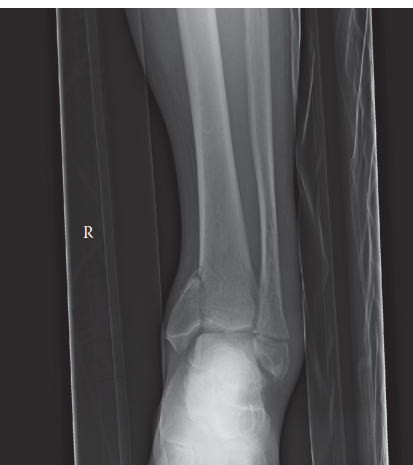

s 1 year down the line following an open fracture of the tibia treated with an intramedullary nail. 1. Descri…